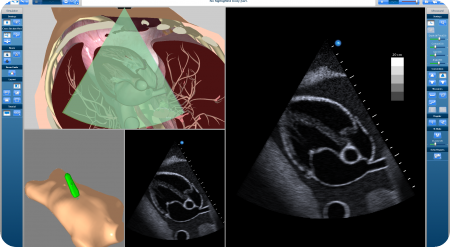

CAE_vimedix_450_247_s_c1

CAE Healthcare’s latest ultrasound simulators, the Vimedix. Courtesy of CAE Healthcare.

The visual technology inspired our virtual reality ultrasound, which is very realistic. Ultrasound is unique in comparison to other imaging methodologies. Unlike CT or MRI scanning where the machine produces the images, ultrasound is completely operator-dependent.

An_Acheived_TCP_450_247_s_c1

Screenshot of the software actively simulating the real time movement of the trainee. Courtesy of CAE Healthcare.

If you do an echo exam of the heart, you need to be exactly between 2 ribs, avoiding all the shadows and artifacts of the lungs and ribs to capture the right image. Deviate a few degrees or millimeters to the left or right and you miss the image. In our simulator, the manipulation and tracking of the ultrasound probe is extremely accurate. That's key to acquiring the skills that are central to proper ultrasound scanning.